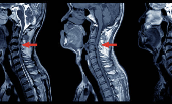

2. 경추 디스크 (목디스크)

목 디스크가 탈출해 팔로 내려가는 신경을 누르면 손끝까지 저림이 생깁니다. 손가락 저림과 함께 목, 어깨, 팔 통증이 동반되기 쉽습니다.

- 특정 손가락 끝 저림 (C6: 엄지, C7: 중지, C8: 새끼손가락)

- 어깨

팔손끝으로 이어지는 전기감, 방사통 - 목을 뒤로 젖히면 증상 심화

- 목 통증이나 뻣뻣함 동반